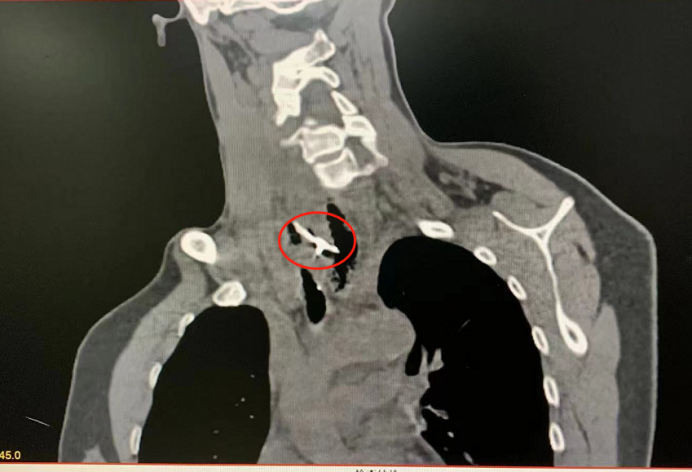

近日,50岁的吴女士(化名)吃饭时误吞了鸡骨头,当时虽有明显咽痛,却未及时就医,拖到第三天才前往广州医科大学附属第三医院耳鼻喉科治疗。经食道CT检查,医生发现鸡骨头已经刺破了吴女士的食道,并出现了积气、化脓等并发症,手术取出碎骨一量竟约4厘米!术后吴女士恢复良好,已顺利出院。

接诊的广医三院耳鼻喉科医生卢川马上安排她做检查,结果发现骨头停留在食道里,扎穿食道壁,并伴有积气、积脓等严重的并发症,情况比较危险。

图中红圈标注为卡喉的鸡骨

手术中,医生采用硬质食道镜经口手术,克服了感染严重的食道黏膜高度水肿和不断渗血的不利因素,终于发现了紧贴其食道后壁的鸡骨。由于病情拖延,骨头已刺穿左右两侧食道壁,并牢牢嵌顿其中,已出现感染化脓。医生用钳子咬断骨头,顺利将两截断骨顺利取出。